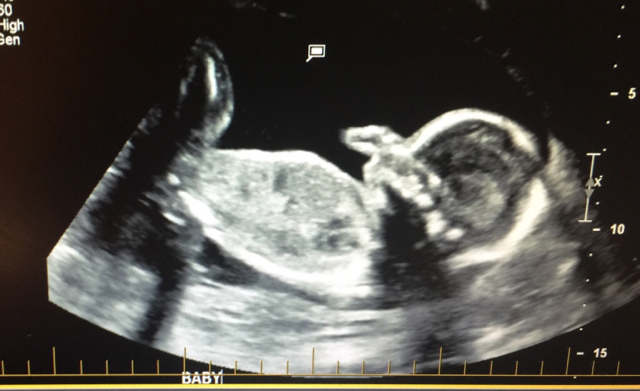

Please any guesses ? Scull theory?